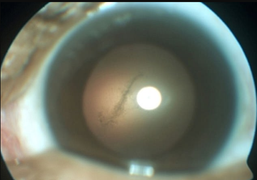

Nữ sinh 15 tuổi ở Đồng Nai bị mất thị lực hoàn toàn mắt trái sau khi tiêm filler để nâng mũi với giá 1,5 triệu đồng.

Ngay sau khi tiêm, cô gái lâm tình trạng đau nửa đầu bên phải, tắc động mạch mắt và mất thị lực mắt phải.

Sau khi tiêm filler, mặt nạn nhân sưng to, mí mắt sụp, vết bầm lan rộng, mắt trái bị hoại tử và đối diện với nguy cơ mất thị lực.

Bị mù mắt trái cùng nhiều biến chứng khác sau khi tiêm chất làm đầy khiến Nguyễn Thị L. suy kiệt nặng nề cả về sức khỏe lẫn tinh thần, nhưng trong thời điểm khó khăn nhất, người bạn trai ngoại quốc vẫn luôn sát cánh cùng cô.